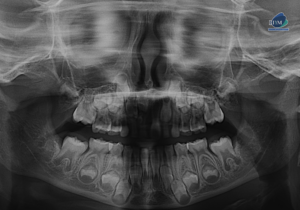

Paciente femenino de 13 años de edad, es referido al Instituto de Diagnóstico Maxilofacial – IDM para evaluación general. En la radiografía panorámica (Figura 1),

Paciente masculino de 16 años de edad, es referido al Instituto de Diagnóstico Maxilofacial – IDM para evaluación general. En la radiografía panorámica (Figura 1),

Paciente masculino de 30 años de edad, es referido al Instituto de Diagnóstico Maxilofacial – IDM para evaluación general. En la radiografía panorámica (Figura 1),

Paciente femenino de 10 años de edad, es referido al Instituto de Diagnóstico Maxilofacial – IDM para evaluación general. En la radiografía panorámica (Figura 1),